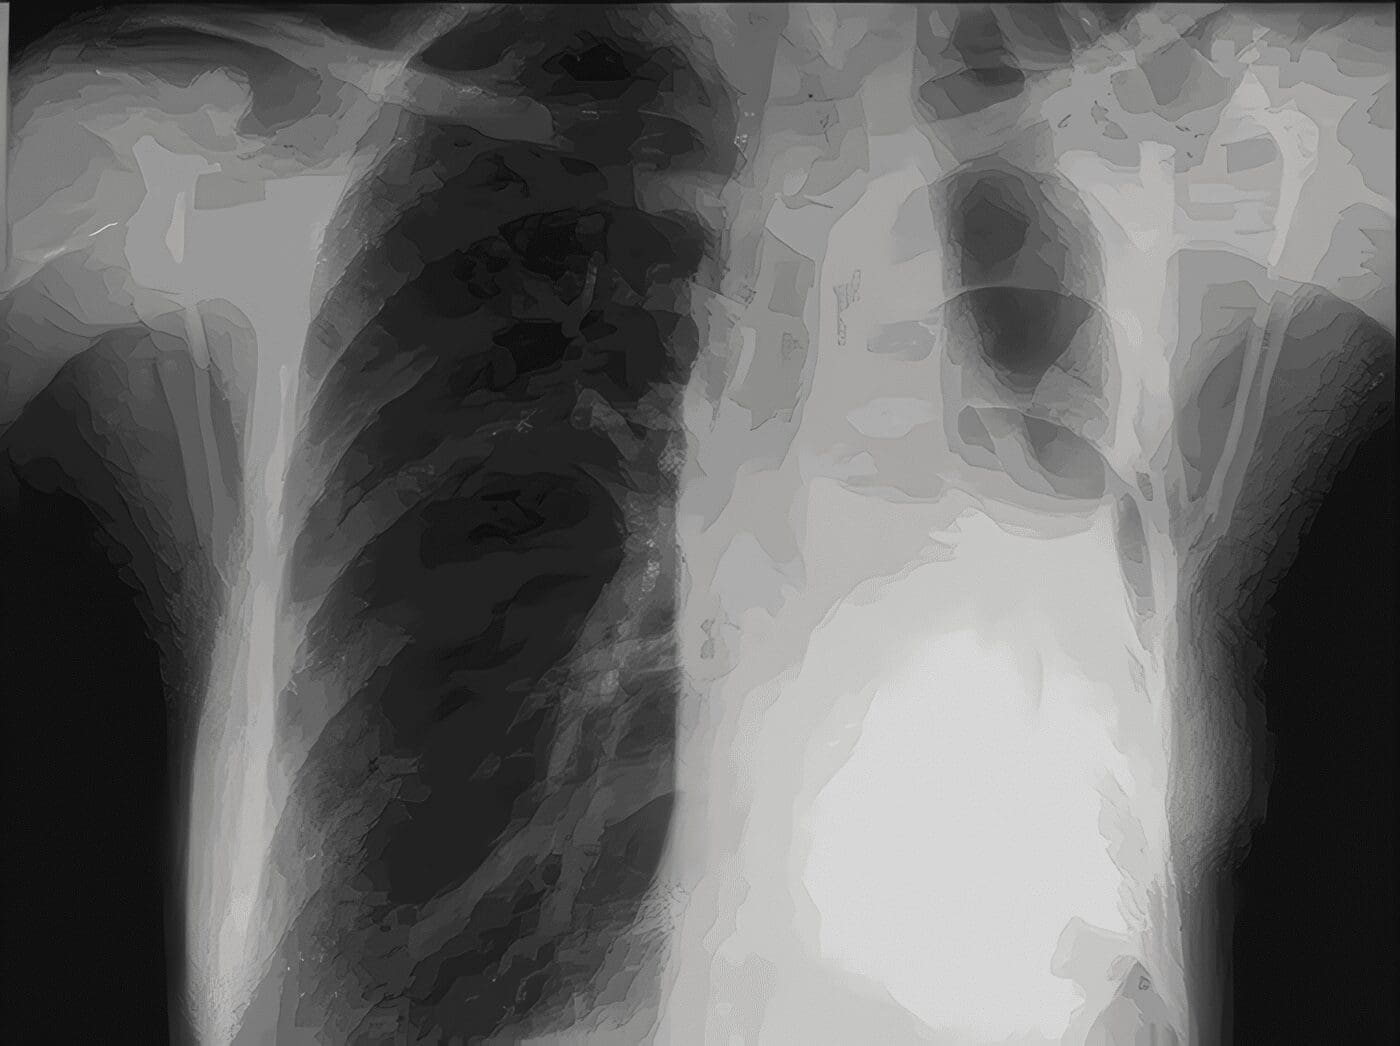

Los síntomas más frecuentes fueron tos y fiebre mayor a 38 grados (en nueve de 10 pacientes), disnea (en cinco pacientes), dolor pleurítico (en cinco pacientes) y esputo hemoptoico (en cuatro pacientes).

Seis pacientes desarrollaron fístula aérea persistente de moderado a alto flujo evidenciada por burbujeo en el sistema de drenaje, en un paciente se demostró caída del nivel hidroaéreo en la radiografía del tórax y en otro un neumotórax a tensión.